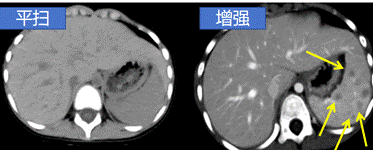

CT平扫是普通CT扫描,用于全身各部位检查,能提供病变的初步定位,显示病灶的基本形态、大小等,是临床常规的检查方法。平扫是相对于增强扫描而言,是最普通、最基础的CT检查。然而,有些疾病或病变在平扫CT上可能呈现模糊或难以辨认的特征,这时就需要进行CT增强扫描。

增强CT是在检查前先将含碘的对比剂注射进静脉后再进行扫描,是对平扫CT的补充,由于碘对比剂进入血液后,血液中含碘浓度升高,在病变部位与器官中的碘浓度形成密度差异,这样显影就更加清晰,更有利于对病灶范围、数量及性质等做出判断。因此,增强扫描是对CT平扫的补充,可以理解为CT平扫的升级版。

显示病变的边缘和内部结构:有些病变在平扫CT上可能难以清晰地显示其边界和内部构造。增强CT可以使病变的边缘更加清晰,有助于医生准确定位和评估病变的性质。

提高病变的检出率:在一些情况下,疾病早期病变较小,或者病变与周围正常组织的密度差异较小,平扫CT可能无法明确显示病变。通过增强CT,病灶或异常区域的对比度增加,病变更容易检测和诊断。